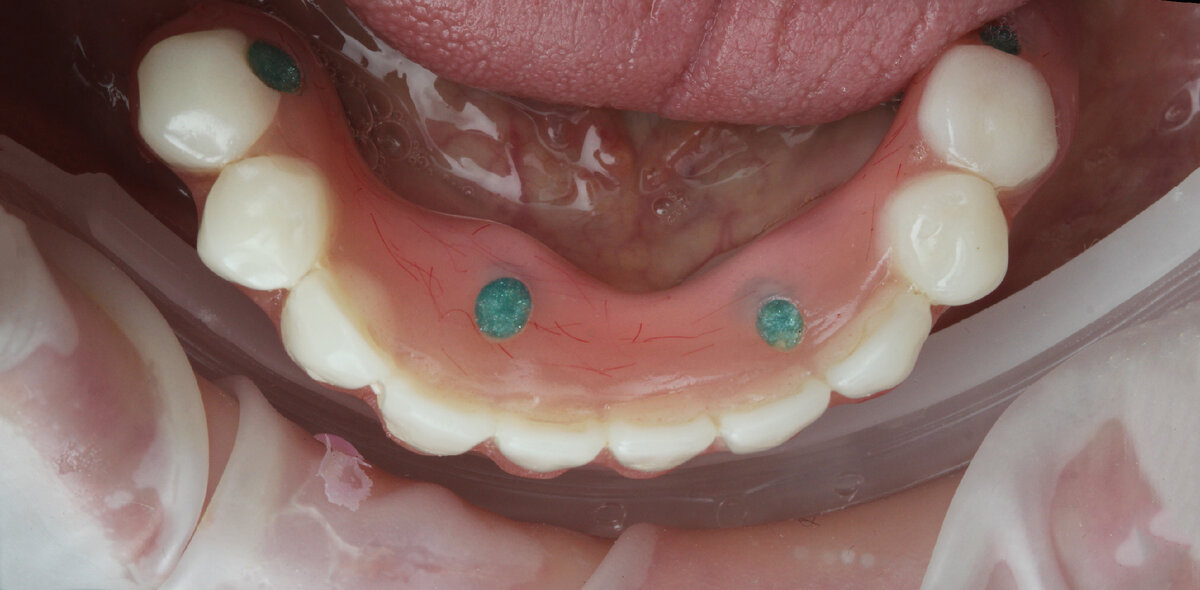

Диагностическая постановка.

После отливки модели по индивидуальной ложке была подготовлена Диагностическая постановка, для примерки в полости рта (восковой прототип будущей работы с гарнитурными зубами).

Диагностическая постановка отправляется на примерку.